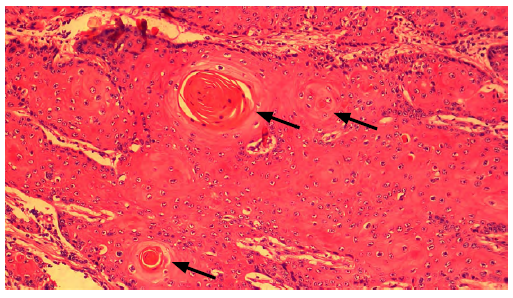

Los hallazgos microscópicos evidenciaron proliferación neoplásica maligna de origen epitelial con un patrón de crecimiento invasivo multilobular en glándula de meibomio y dermis superficial y profunda (figura 4) , islas o nódulos de diferentes tamaños, algunas formando estructuras quísticas que contienen abundante queratina laminar concéntrica-perlas de queratina (figura 5) , adicionalmente, núcleos redondos, ovalados, alargados e irregulares y úlcera focalmente extensa con múltiples áreas de necrosis (figura 6), fibrina severo infiltrado mixto linfoplasmocitario eosinofílico y supurativo difusa, dermatitis mixta ulcerativa y necrótica severa difusa con sobreinfección bacteriana y adenitis mixta severa difusa.

FIGURA 5 Masa tumoral. Estructuras en forma de nódulo formando perlas de queratina (flecha). Tinción H&E, 4x

El hemograma realizado en el paciente reveló una leucocitosis con eosinofilia y neutrofilia marcada, por lo cual un aumento de los neutrófilos se ha asociado en procesos tumorales y el proceso inflamatorio del evento injuriante, por ser la primera línea celular de defensa inmune; los cambios hematológicos en procesos tumorales evidencian que la anemia es la anormalidad más común encontrada durante la estimación hematológica en animales con neoplasia. No obstante, se ha observado el recuento elevado de leucocitos periféricos, linfopenia y eosinofilia con signos vitales normales (Kashyap et al. 2022), lo que concuerda con lo evidenciado en el cuadro hemático del paciente, aunque no presentó anemia. El diagnóstico de este estudio de caso fue realizado mediante la herramienta de histopatología para identificar inicialmente la neoplasia y de esta manera realizar el tratamiento y abordaje correcto y que, de acuerdo con Carvalho et al. (2005) entre las pruebas diagnósticas, la histopatología es una excelente herramienta para identificarlos hallazgos microscópicos compatibles con un OSCC, cuya neoplasia puede variar desde un carcinoma anaplásico bien diferenciado hasta un carcinoma anaplásico indiferenciado. El carcinoma de células escamosas contiene la presencia de grandes células poliédricas con gran nucléolo dispuestas en cordones con puentes intercelulares que forman nidos de células epiteliales y que contienen laminaciones concéntricas de queratina (Priyanka et al. 2021) y las lesiones pa-tognomónicas microscópicas presentan islas con fácil distinción de perlas córneas rodeadas de células tumorales que pueden ser células escamosas organizadas y atípicas, con núcleos hipercromáticos, citoplasma eosinofílico con queratinización y con infiltración en el tejido subyacente (Cardona et al. 2013). Estas lesiones también se distinguen como perlas de queratina y se caracterizan por células hipertróficas con núcleo grande con alta figura mitótica (Cardona et al. 2016), estas perlas de queratina contienen deposición de fibras de colágeno mezcladas con la queratina presente alrededor de estas lesiones (Al-Mahmood et al., 2022). Es así como los hallazgos microscópicos de la histopatología realizada en este caso clínico coinciden con los patrones de un carcinoma escamocelular reportado en diferentes estudios hasta la fecha.